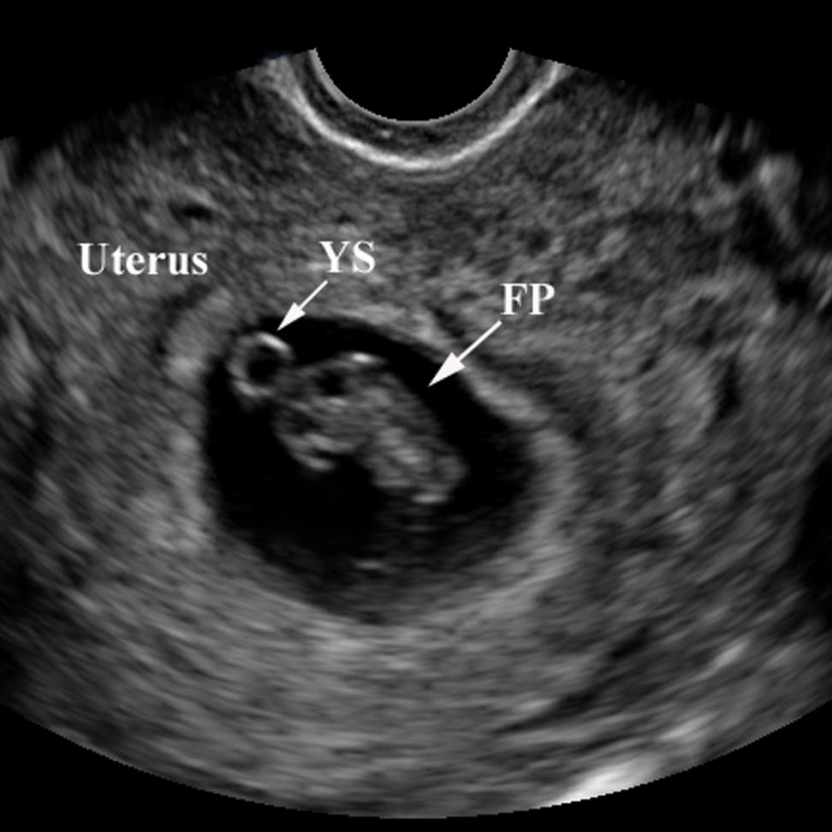

Baby’s growth at 6 weeks pregnant through ultrasound pictures …

The Pregnancy Diaries: I’m 8 weeks pregnant! – Life Education Council

Ultrasound Leadership Academy: Ultrasound in Early Pregnancy — EM Curious

PV Card: Focused 1st Trimester Pregnancy Transvaginal Ultrasound